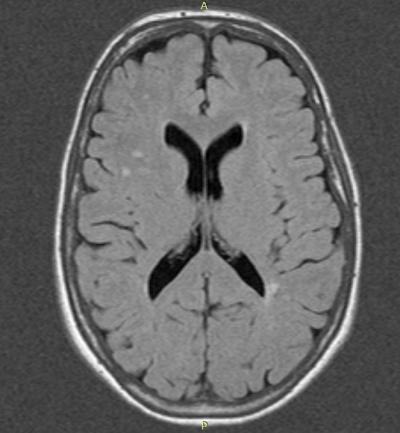

The study also showed that women with migraine had a higher likelihood of having brain changes that appeared as bright spots on magnetic resonance imaging (MRI), a type of imaging commonly used to evaluate tissues of the body.

"An important message from the study is that there seems no need for more aggressive treatment or prevention of attacks," said Mark C. Kruit, M.D., Ph.D., one of the principal investigators, and a neuroradiologist from Leiden University Medical Center, the Netherlands, which led the study. Dr. Kruit and associates evaluated MRIs for changes in the white matter, brainstem, and cerebellum that appeared on the scans as bright spots known as hyperintensities. Previous studies have shown an association between such hyperintensities and risk factors for atherosclerotic disease, increased risk of stroke and cognitive decline.

Standardized measures of cognitive abilities such as memory, concentration, and attention did not show significant losses among people with migraine-associated lesions compared to those without migraine. The brain changes that give rise to the bright spots seen on MRI are unknown. More research is needed to find out if these are related to ischemia and ischemic stroke risk, according to the researchers.